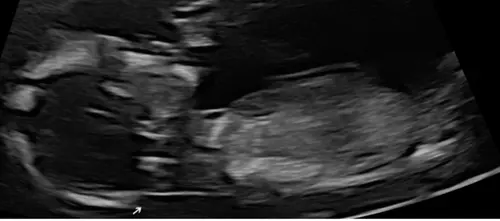

Foto鈥檚 zijn overigens van echo die gemaakt is met 13 + 5

Ik zie dus helemaal niets bij niemand haha! Iemand die bij mijn echo iets ziet?

Ik zie dus helemaal niets bij niemand haha! Iemand die bij mijn echo iets z ...

Buiten een erg lief wipneusje is dit een jongetje 馃挋